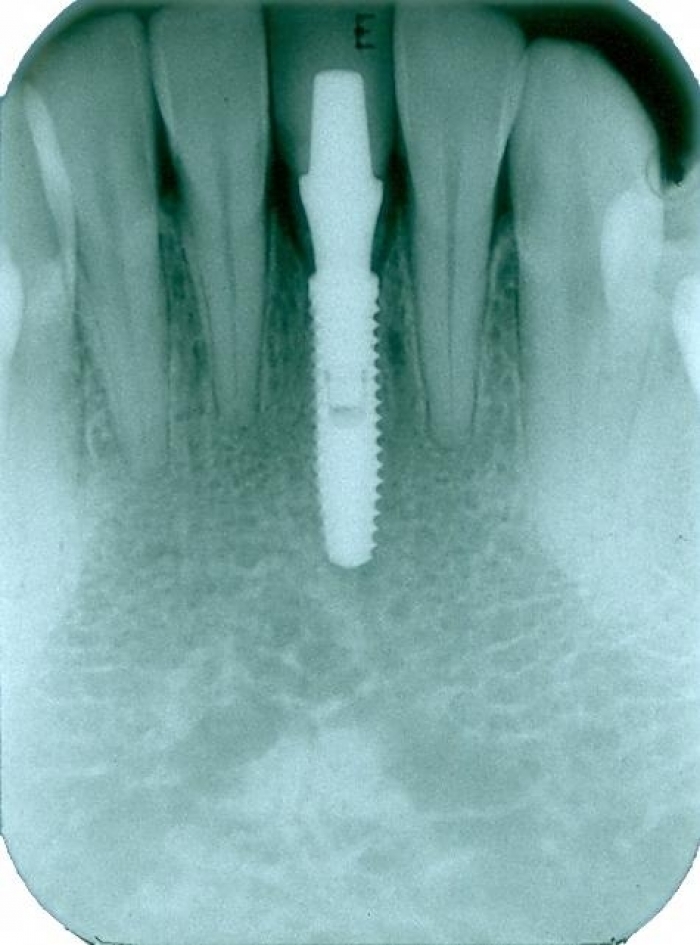

Raio x após extração e instalação do implante e dente provisório imediato

Imagens do dente provisório fixo imediato, no implante Cone Morse Facility